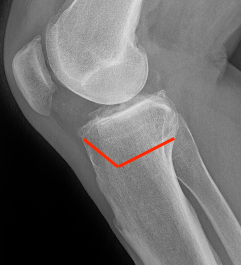

Oblique Osteotomy

- entry is 4 cm distal to joint line

- osteotomy must pass above tibial tuberosity

- aiming for proximal third of the fibula head

- to 10 mm of lateral cortex to avoid lateral hinge fracture

- stay 2 cm below the tibial plateau to avoid intra-articular fracture

- ensure osteotomy is parallel to joint line to avoid altering slope